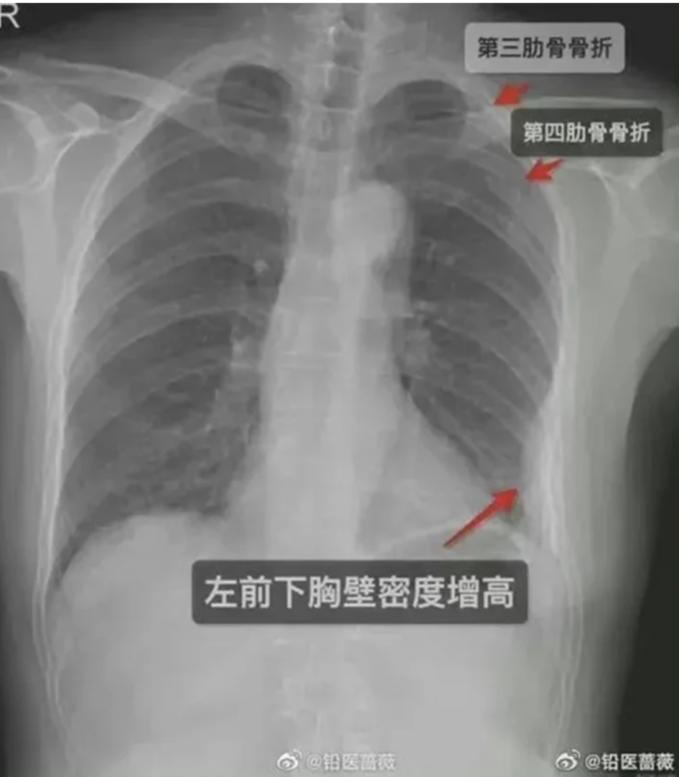

Năm ngày sau, cơn đau không thuyên giảm, cô gái đến bệnh viện kiểm tra. Kết quả chụp X-quang cho thấy cô bị gãy ba xương sườn, gồm hai chiếc ở bên phải và một chiếc ở bên trái. Cô phải nghỉ việc khiến thu nhập giảm, chi khoản tiền lớn cho viện phí và các dịch vụ chăm sóc vết thương.

Kết quả chụp X-quang cho thấy cô gái trẻ bị gãy 3 xương sườn sau lần ôm chặt của đồng nghiệp. Ảnh: Odditycentral